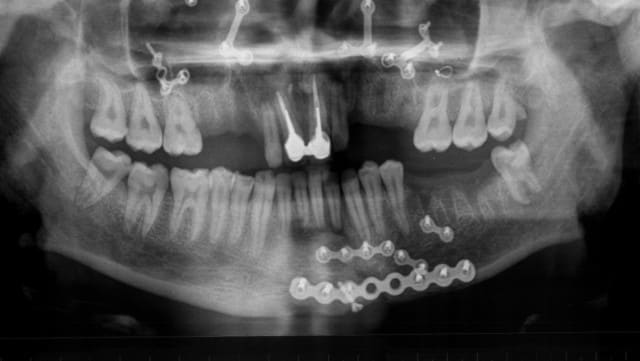

si jamais tu decides de garder les laterales,envoie des retros:sur la pano,luxation sur la 12?la 22 intrusee?pas assez clair

je t'envoie la pano d'après extractions, elle est parlante.

voilà

Pano2 lztpwe - Eugenol

Tu est sure que les centrales sont perdues ?

oui, hélas, les centrales sont perdues.

je réfléchis à l'intérêt éventuel de garder les latérales.

d'un côté, en les gardant, j'ai besoin de huit implants, en les supprimant, je peux me contenter de six, avec une gestoin esthétique beaucoup plus simple.

au fait, t'as vu alhoun, t'as une endo à faire sur la 47!

pour la 46, c'était plus simple, mais impossible de prendre les canaux mésiaux.

de toute façon, je refais une pano après les implants.

La 22 semble fracturée sur la pano, mais c'est peut être un artefact, il faudrait vérifier avec une rétro, mais si c'est le cas, tu es évidemment mal barré pour une traction.